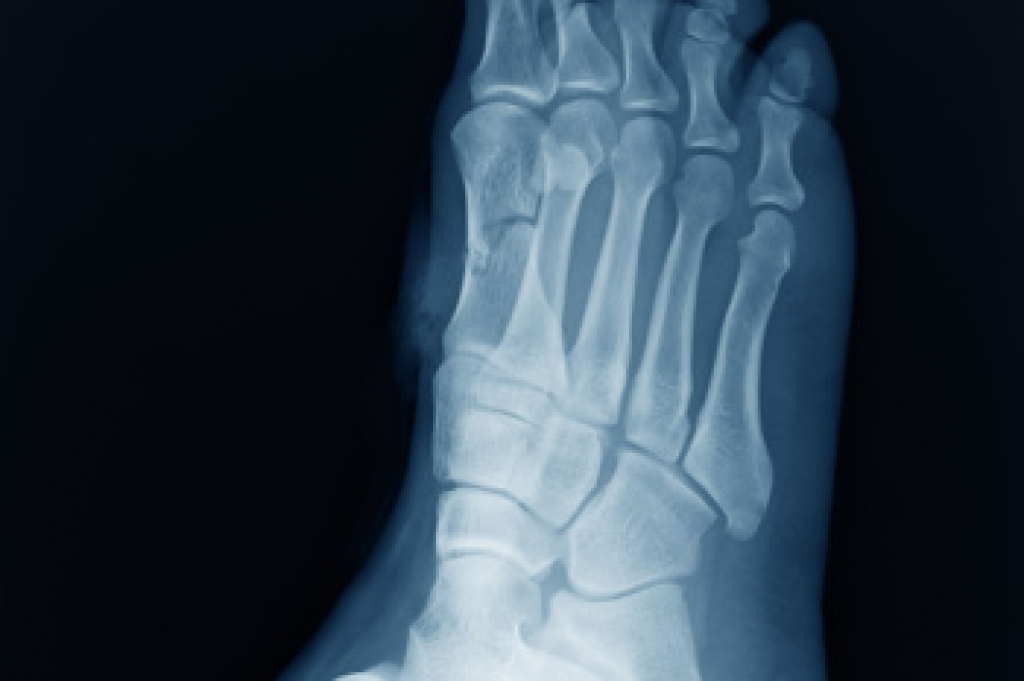

Causes of Heel Pain

Heel pain is often associated with plantar fasciitis. The plantar fascia is a band of tissues that extends along the bottom of the foot. A rip or tear in this ligament can cause inflammation of the tissue.

Achilles tendonitis is another cause of heel pain. Inflammation of the Achilles tendon will cause pain from fractures and muscle tearing. Lack of flexibility is also another symptom.

Heel spurs are another cause of pain. When the tissues of the plantar fascia undergo a great deal of stress, it can lead to ligament separation from the heel bone, causing heel spurs.